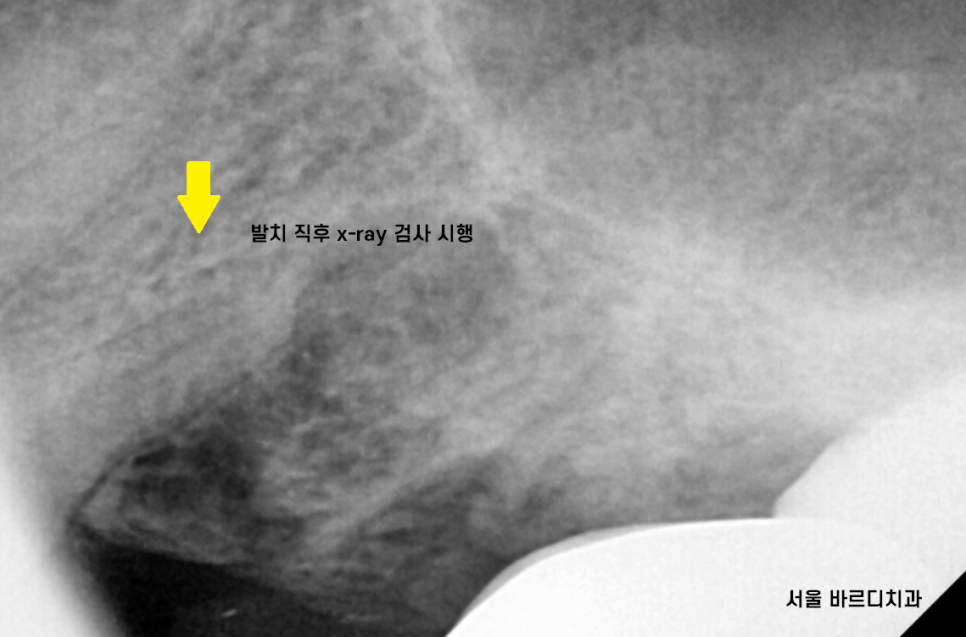

23.07.11

수술 당일 발치를 진행하고

x-ray를 찍었습니다.

남아있는 치아 뿌리는 없는지?

눈으로 1차 확인하였지만

한 번 더 안전한 과정을 거친 후 수술을 진행